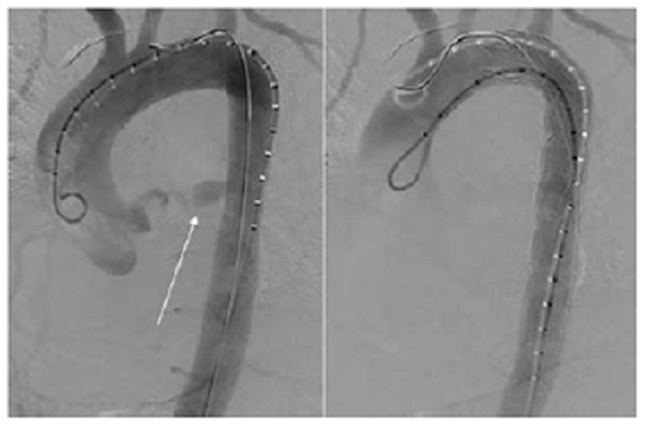

Fue sometida a una corrección endovascular de ruptura aórtica torácica, con endoprótesis recubierta (Medtronic Valiant VAMF2222C 150TE™), la cual se desplegó respetando el orificio de la arteria subclavia izquierda y se logró el cubrimiento exitoso del sitio de ruptura, sin evidencia posterior de extravasación con medio de contraste (figura 2).